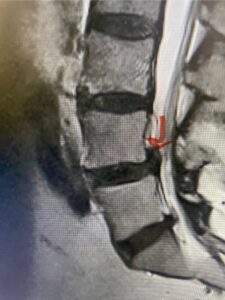

The next patient is a 56-year-old morbidly obese female who had progressive leg pain and weakness. She was over 320 lbs and did not have diabetes either. On MRI she had a massive disc herniation spanning the L3-4 and L-4 interspaces, centered behind the L4 vertebral body (Fig 3A and B). She also had an L4-5 spondylolisthesis. There were opinions that the disc emanated from the L3-4 disc space, but because of spondylolisthesis and on careful inspection of the MRI, there was a high chance the disc herniation had instead emanated from L4-5 (Fig 4). She had conservative treatment including epidurals but had worsening strength and numbness. She was scheduled electively for surgery, but then fell, and broke her ankle. She could not walk, particularly due to the pain down her leg. She was taken to the operating room urgently after she was cleared medically. She had no issues cardiologically and was taken to the operating room. The patient underwent a laminectomy that extended above the L3-4 disc space to below the L4-5 disc space. We encountered mainly centered on the left at the level of the L4 vertebral body and massive disc herniation that created a huge cavity in the lumbar canal. It was covered in an interesting thin membrane that we dissected off the disc herniation (Fig 5). Postoperatively the patient did experience significant relief of pain, but some improvement of strength. In combination with the ankle fracture and the extent of preoperative weakness, the patient required extensive rehab. The patient also developed a seroma and some wound drainage issues that were treated locally.

Fig 4: Sagittal T2-weighted lumbar MRI demonstrating an L4-5 grade 1 spondylolisthesis with obvious emanation of the disc herniation from the L4-5 level (red arrow)